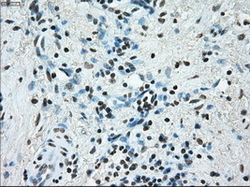

- Submitted by

- LSBio (provider)

- Enhanced method

- Genetic validation

- Main image

- Experimental details

- Immunohistochemical staining of paraffin-embedded Adenocarcinoma of endometrium tissue using anti-ERCC1 mouse monoclonal antibody. (Dilution 1:50).